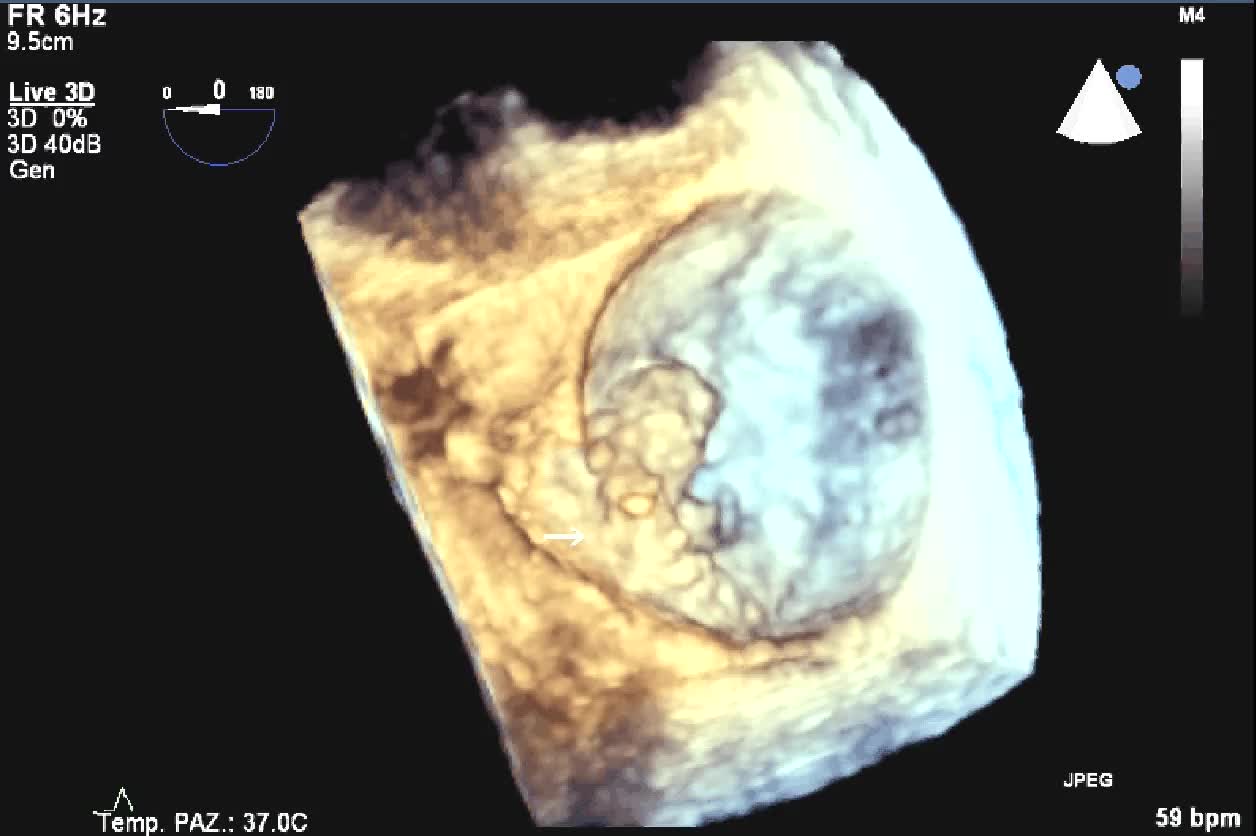

Distacco di protesi meccanica mitralica da endocardite infettiva con severo rigurgito paraprotesico

Distacco di protesi meccanica mitralica da endocardite infettiva